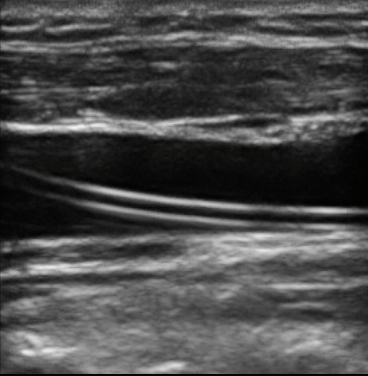

M-Turbo:IJV 长轴中的导管图像

M-Turbo:IJV 长轴中的导管